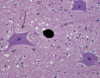

Neuron

Astrocytes